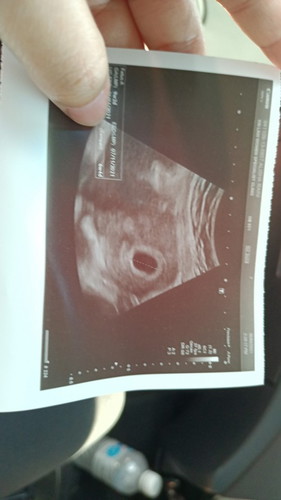

sm mcm sy tp sy bleeding dh 2 minggu. dh sebulan bleeding sbb doc ckp ad kntung tp ksong. kena tggu dlu. sok last kali ke 3 sy scan. kalo x, kena cuci. hrp sok ada keajaiban.kntung still molek walau sebulan dh bleeding. nie pic scan kali ke 2.. sy still doa sok ada lh brita gmbiraπ’